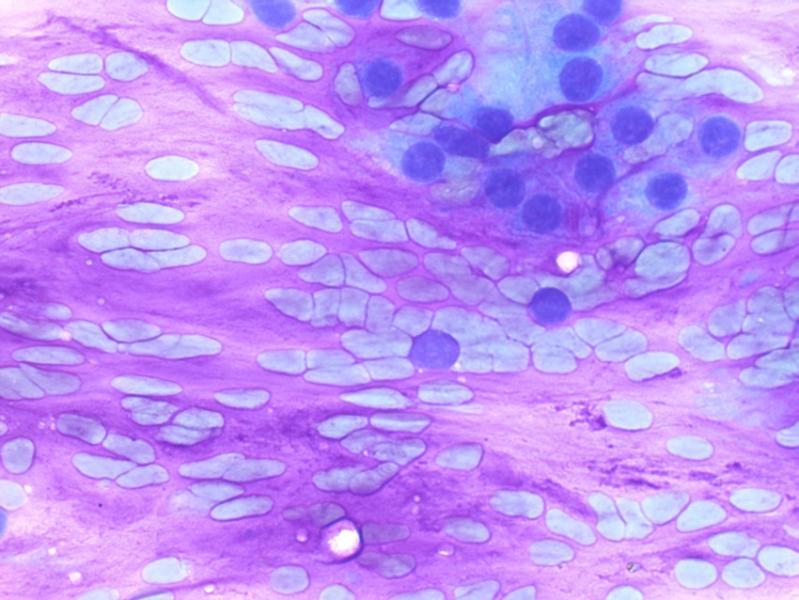

Het mooiste beeld: microscopische kunst

Wat is het mooiste beeld? 12 inzendingen ontving de NTvG-redactie naar aanleiding van de oproep aan pathologen om hun mooiste foto van een microscopisch preparaat in te sturen. In tegenstelling tot de fotowedstrijd van vorig jaar was de jurering dit jaar niet makkelijk. Wij hadden verwacht dat we louter…